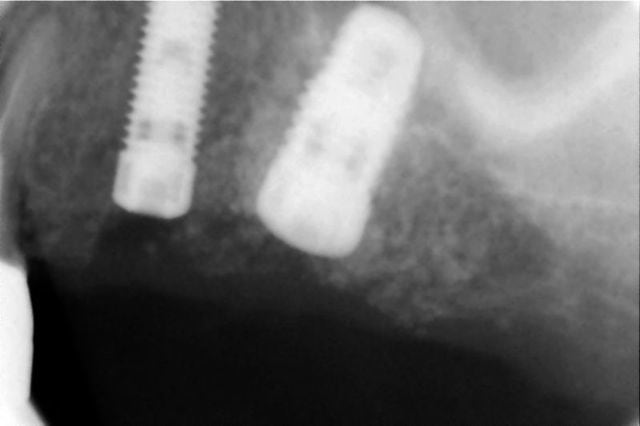

bon, je vous livre à chaud mes impressions positives et négatives:

ci joint 6 photos avant pendant et après,

je n'ai donc pas aplani comme conseillé,

j'ai passé le forêt pilote puis les ostéotomes 2.7 et 3.2,

le cliché de contrôle avant pose de l'implant montre bien le dôme du matériau de comblement, jusque là tout allait bien et je pensais que le plus dur était fait,

c'est après que j'ai été ennuyé:

j'ai commencé à visser à la main le WP de 5 mm

et j'ai rencontré une résistance quand il était à ras de la corticale V alors que du côté palatin j'avais une déhiscence de 2 mm ( normal je n'avais pas aplani)

j'ai eu l'impression qu'il perdait en stabilité et tournait sur lui même, curieux pour un os tendre?

la situation ne me plaisait pas et je l'ai dévissé, puis

j'ai élargi un peu au counterbore, et j'ai revissé,

aucune amélioration donc le problème était soit à l'apex de l'implant( perforation trop étroite pour le passage d'un implant cylindrique), ou alors le long des parois, auquel cas j'aurais dû passer un ostéotome de 3.7, ou même 4.2 ce qui me paraissait un peu trop pour un WP sur un os peu dense,

j'ai quand même réussi en changeant un peu l'inclinaison à le bloquer manuellement à 40 Ncm et sans déhiscence

qu'est-ce qui a pu résister au vissage de l'implant:

1- un os trop dense donc dernier ostéotome trop étroit?

2- un orifice de perforation de la corticale sinusienne trop étroit de 3.2 mm pour un implant de 5 mm non conique ?

3- autre chose que je n'ai pas vu ?

en tout cas, sur les clichés, le beau dôme que l'on voit avant implantation a disparu après pose de l'implant; où est le matériau?